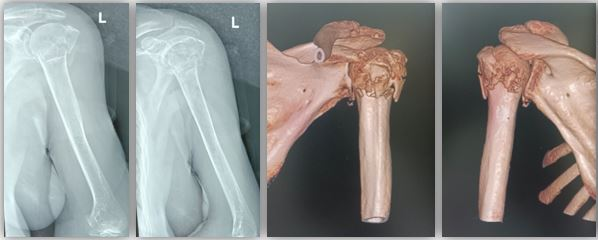

近日,一名88歲的患者因不慎跌倒,左側(cè)手臂無法活動,西京醫(yī)院骨科孟國林副教授接診后,經(jīng)過詳細(xì)檢查診斷為左側(cè)肱骨近端粉碎性骨折,范圍累及肱骨頭和大結(jié)節(jié)、小結(jié)節(jié),更加棘手的是該患者患有嚴(yán)重骨質(zhì)疏松,骨組織如同“蛋殼樣”,骨皮質(zhì)薄弱、肱骨頭空虛。

術(shù)前,根據(jù)老人受傷肢體三維CT影像數(shù)據(jù),個(gè)性化設(shè)計(jì)定制髓內(nèi)支撐假體系統(tǒng),包括肱骨髓內(nèi)主釘、肱骨頭動態(tài)穩(wěn)定組件、肩袖固定等組件。